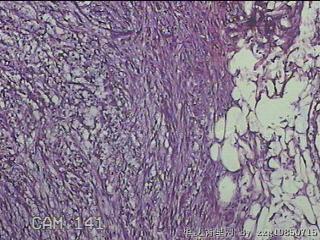

左肘部包块

性别

男

年龄

39

临床诊断

左肘部肿物:炎性脂肪瘤

一般病史

发现左肘部肿物1周。

标本名称

大体所见

灰白粉红色组织2x1.8x0.3㎝一团,表面结节状,光滑,切面灰白粉红色,质软。

图4